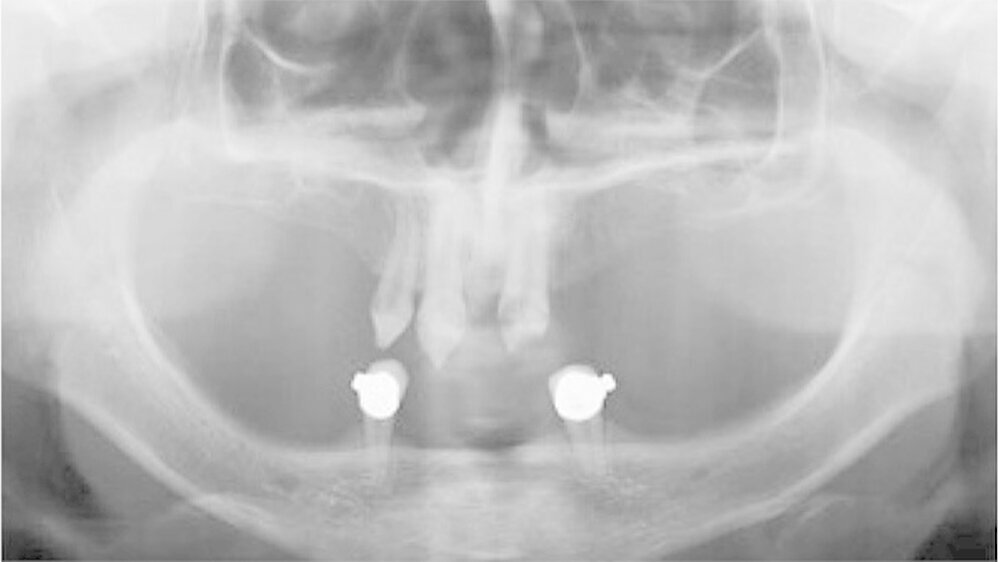

Der bei Behandlungsbeginn 14-jährige Patient war mit einer neun beziehungsweise fünfjährigen Prothese im Unter- beziehungsweise Oberkiefer versorgt (Abb. 2 und 3). Die angelegten Zapfenzähne 12, 11 und 21 waren bereits mehrfach konservierend restauriert und wiesen diverse Stellen mit Sekundärkaries auf. Die Kronenränder der Zähne 33 und 43 waren deutlich sondierbar. Der Kieferkamm im Unterkiefer war aufgrund der fehlenden Zahnanlagen sehr schmal (Abb. 4 bis 6). Die Panoramaschichtaufnahme zeigte das reduzierte vertikale Knochenangebot (Abb. 7). Da die Vitalerhaltung der wenigen Restzähne aufgrund des jungen Alters des Patienten unbedingt anzustreben war, wurde als Behandlungsziel im Ober- und Unterkiefer eine Versorgung mit Hybridprothesen, retiniert auf Teleskopkronen, festgelegt.

Bei dieser bei Behandlungsbeginn 16-jährigen Patientin waren seit Geburt nur die beiden ersten Molaren im Oberkiefer ausgebildet. Die Folge waren schmale und niedrige Alveolarkämme mit einem flachen Gaumengewölbe (Abb. 16 und 17). Die röntgenologische Abbildung bestätigte das geringe vertikale Knochenangebot. Eine Formanomalie der Zahnwurzeln ließ auf taurodonte Molaren schließen. Beide Molaren wiesen ausgedehnte kariöse Läsionen auf (Abb. 18).